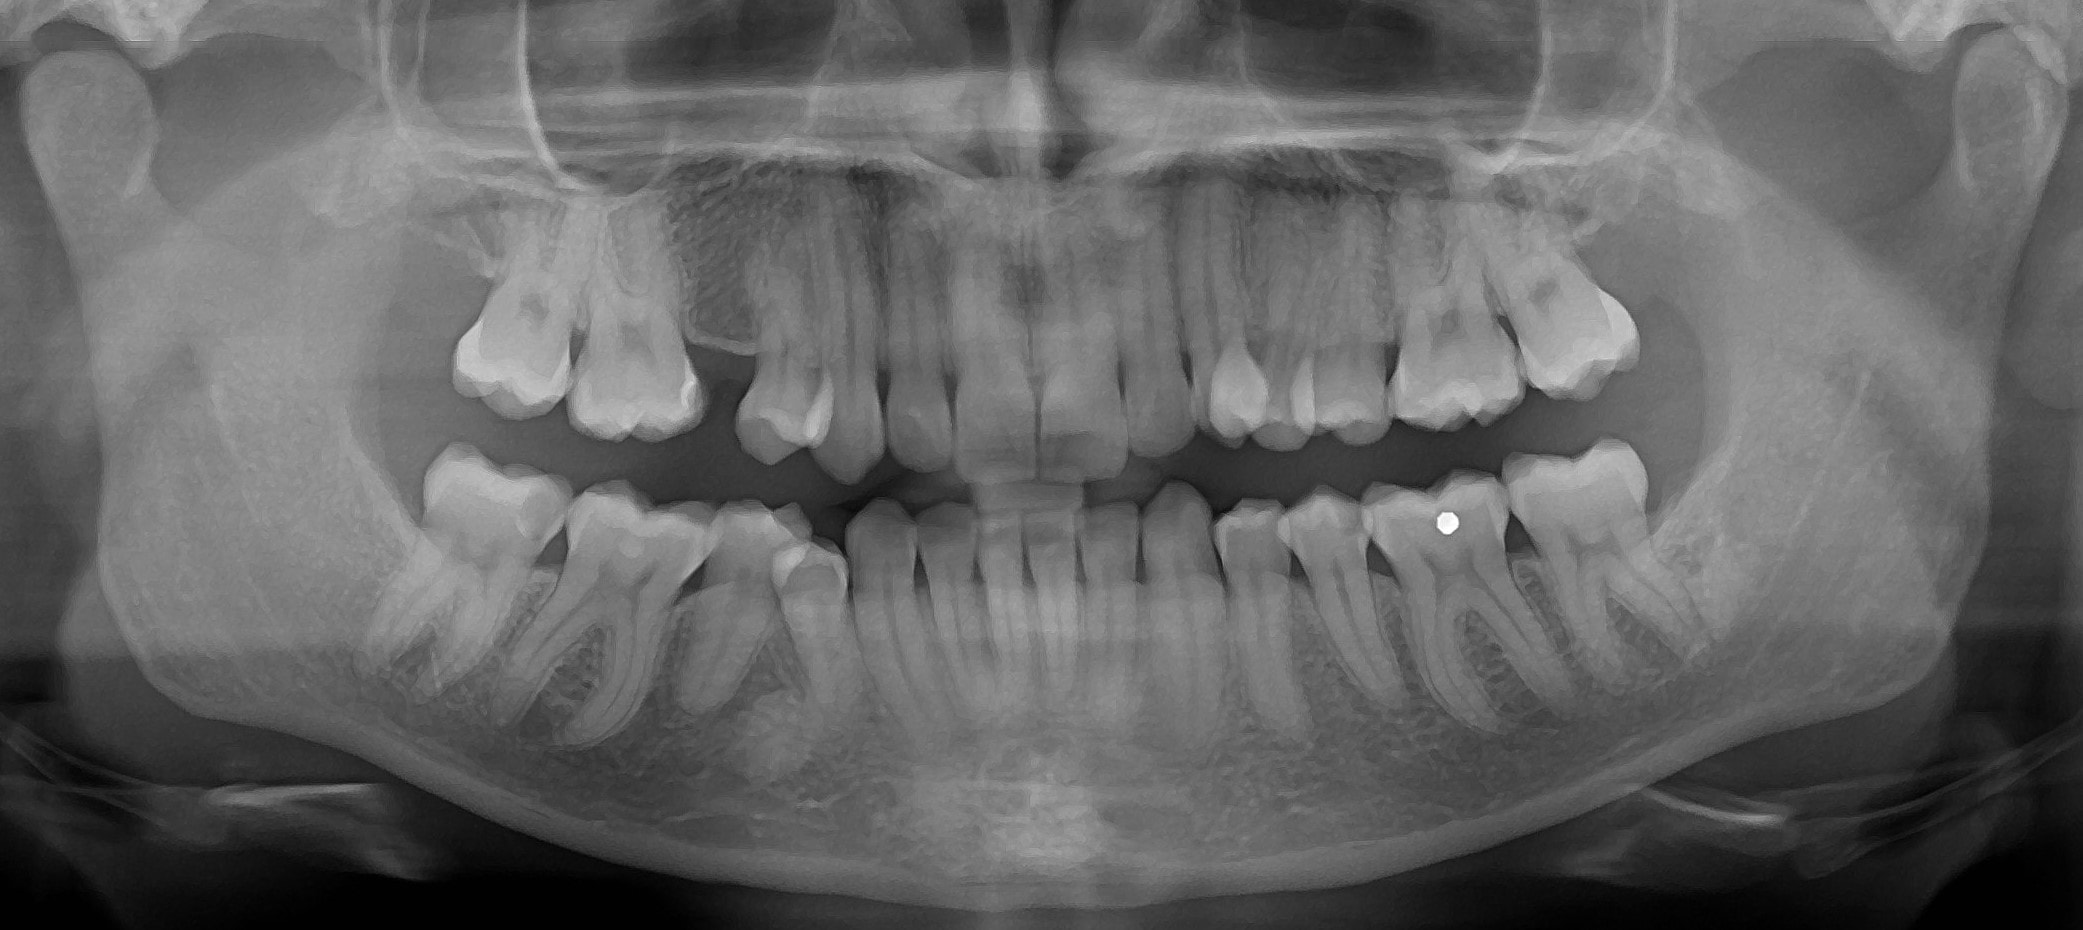

Panoráma röntgen

Panoráma („körbeforgós”) röntgen alatt egy olyan, kétdimenziós felvételt értünk, mely a teljes alsó-felső fogívről megfelelő képet ad, értékelhető rajta az állkapocsízület, valamint az arcüreg is. A foggyökerek és a fogak koronája is jól látható. A röntgen készítése során a röntgenfilm és a röntgensugár a vizsgálni kívánt terület körül forog, egymással szemben elhelyezkedve. Az elülső fogak területére a röntgenkép készítése során sajnos rávetülnek a nyakcsigolyák, így ez a terület kevésbé pontos, éles. Mivel egy körívet egyenesítünk ki, emiatt az oldalsó fogak területe is enyhén torzulhat, nehezebb a kontaktpontoknál keletkező fogszuvasodás felismerése. A panoráma röntgen kiváló diagnosztikus felvétel az általános fogászati állapot megítélése. Sokszor használjuk góckutatás során, hiszen egy röntgenfelvétel készítésével számos területről nyerhetünk diagnosztikus ismeretet. Sugárterhelése minimális.